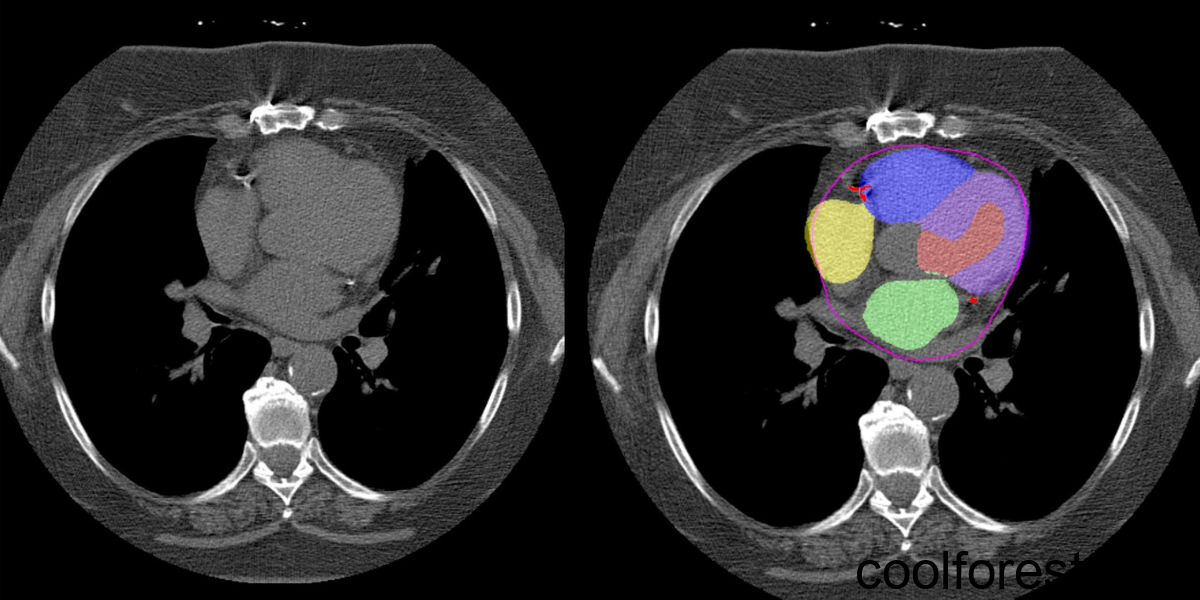

AI is applied to CT scans to automatically segment different heart chambers and quantify arterial plaque. Non-contrast CT slices (left) with superimposed segmentations (right). One model segments CAC (shown in red) while another model segments the four different heart chambers (shown in yellow, blue, purple, and green). Credit: Slomka laboratory/Nature Communications; see licensing information below.

The researchers combined two previously validated algorithms—one developed by Slomka and colleagues that measures CAC, and another that can segment cardiac chamber volumes—to analyze routine chest CT scans (i.e., low-dose scans with no contrast and no gating). They evaluated scans from 24,354 patients who had CT performed as part of the National Lung Screening Trial and identified several cardiac factors that were associated with an increased risk of death, such as a large amount of CAC and increased mass or volume of specific heart chambers. What’s more, the researchers found that combining all the factors together (including clinical data like age and medical history) was a better predictor of death than any one factor alone.